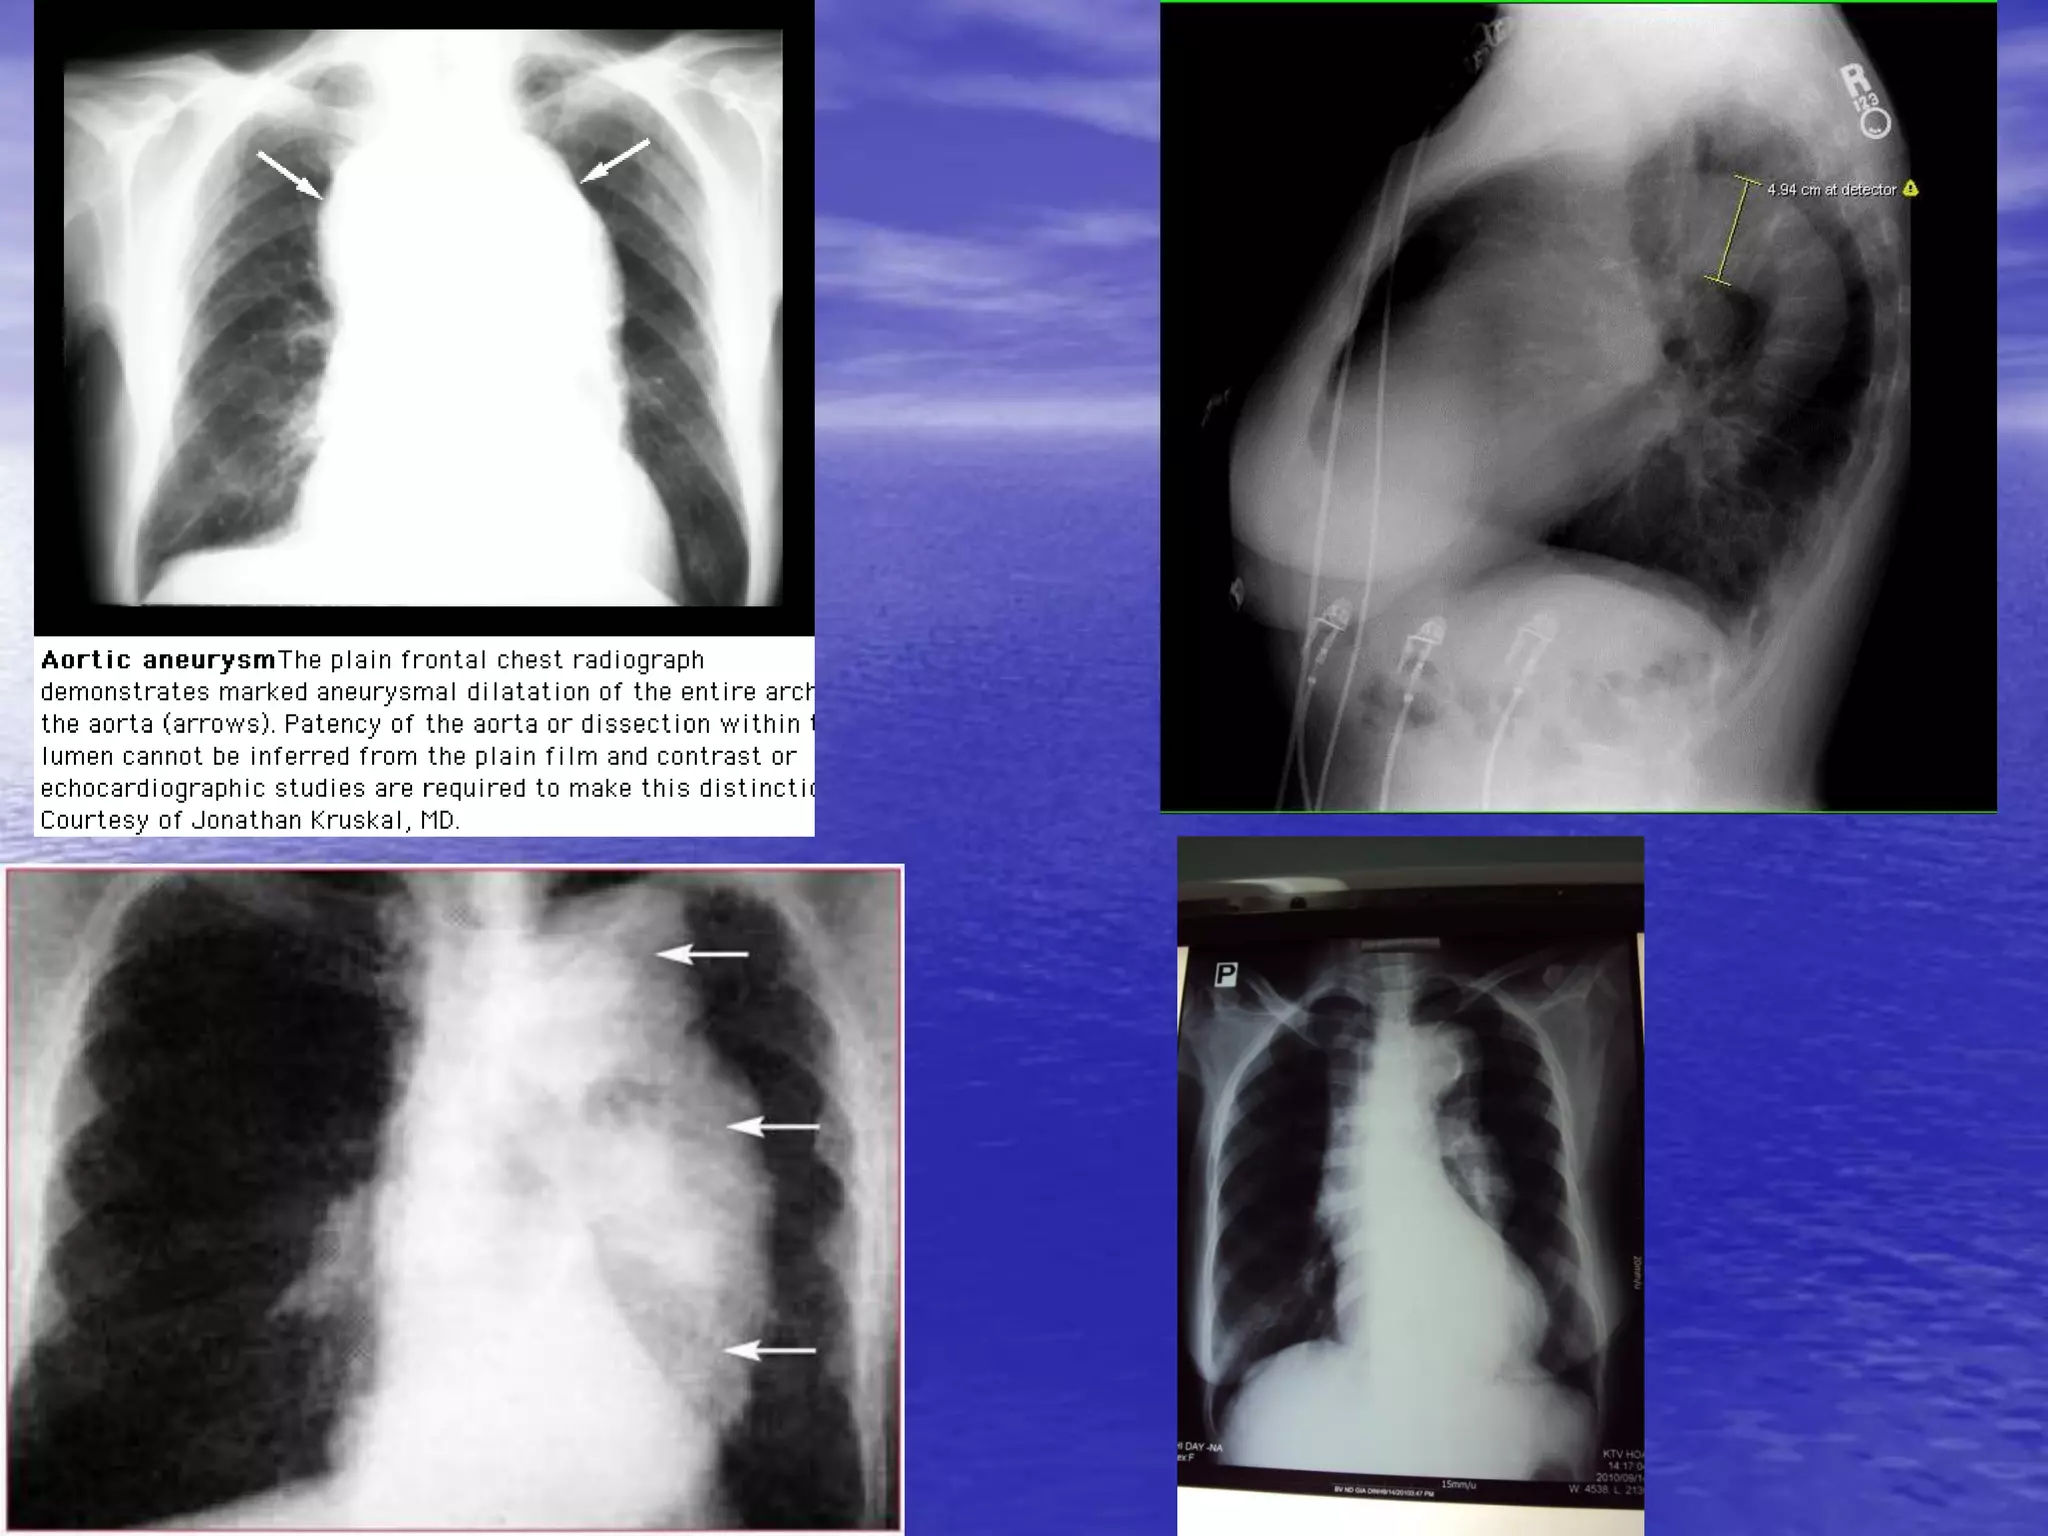

1 số hình ảnh khác

1 số hìnhảnh khác